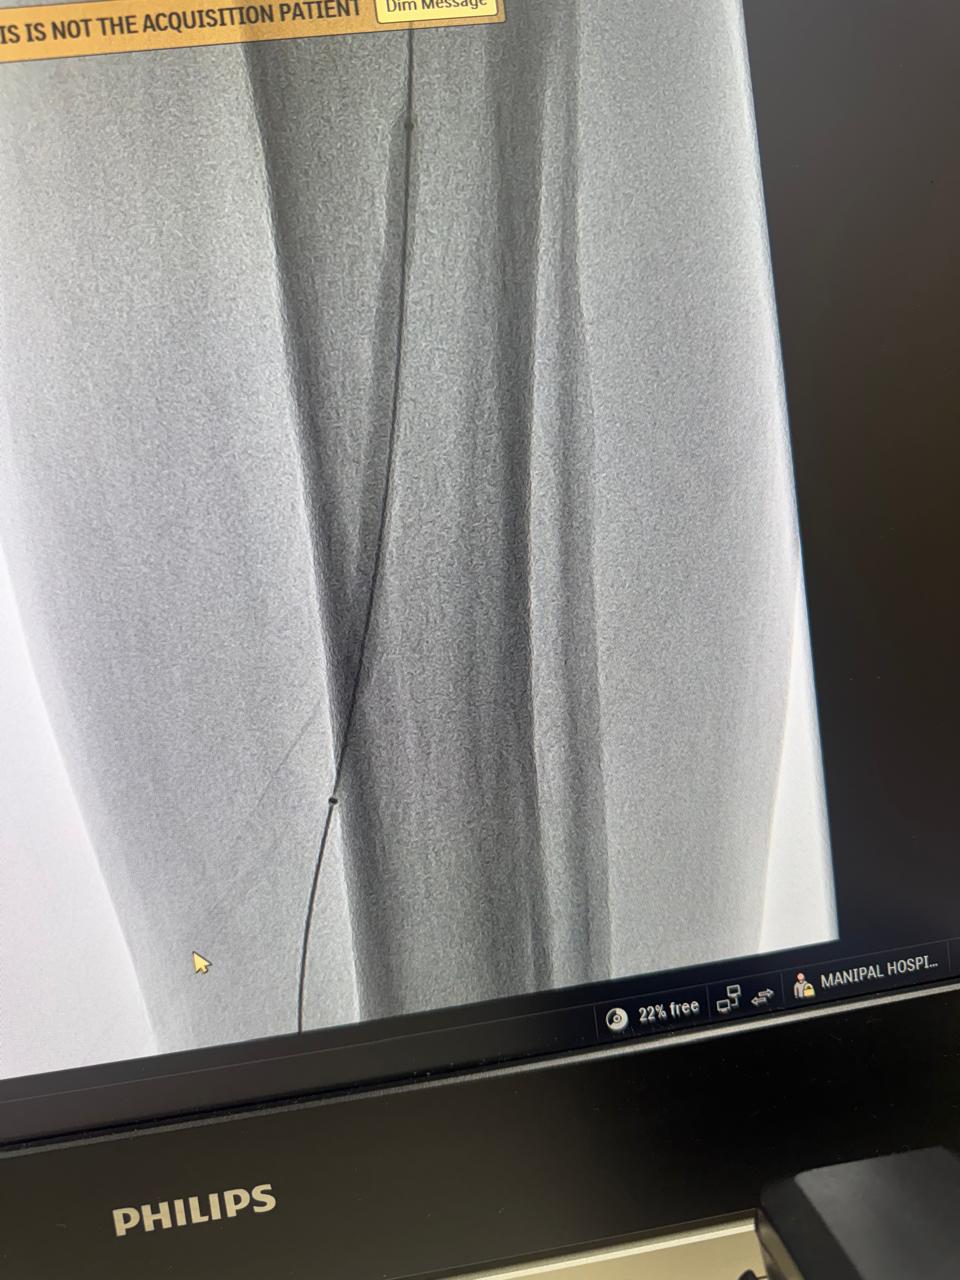

Gross hemoptysis in known case of pulmonary tuberculosis, bronchial artery embolization done